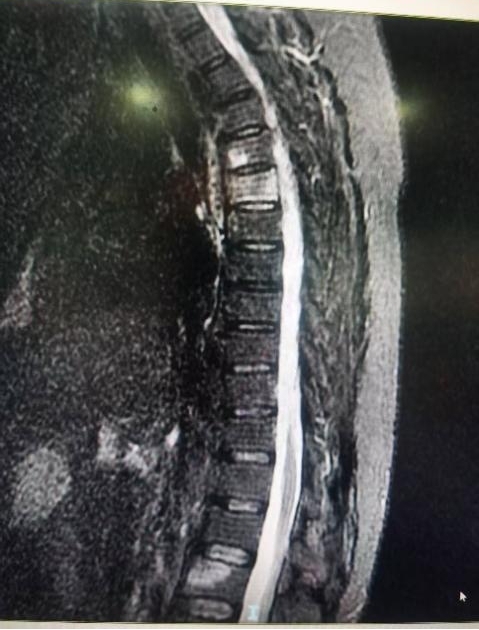

患者,女,53岁,甲状腺癌术后2年,胸4、5及腰2椎体多发骨转移,胸背部无法药物控制的疼痛,即将病理性骨折。胡勇教授团队将MRI、3D-CT及PET-CT图像融合数据输入手术机器人进行精准规划设计,同步完成了3椎体的微创杂交手术,手术历时55分钟,术后无神经损伤并发症发生,患者疼痛消除,术后第二天即可下地行走。

胡勇指出,对于上胸椎及颈胸段椎体病变,由于其特有的解剖结构,以往被视为经皮微创手术禁区。数字技术和人工智能的发展和应用,极大降低了高危手术的风险,提高了操作的精准性和手术的疗效,使得常规技术不可能的手术成为可能,提高了患者的生存质量和生存期。近年来,我院骨病骨肿瘤外科利用手术机器人辅助成功开展了近百例此类手术,造福此类患者。